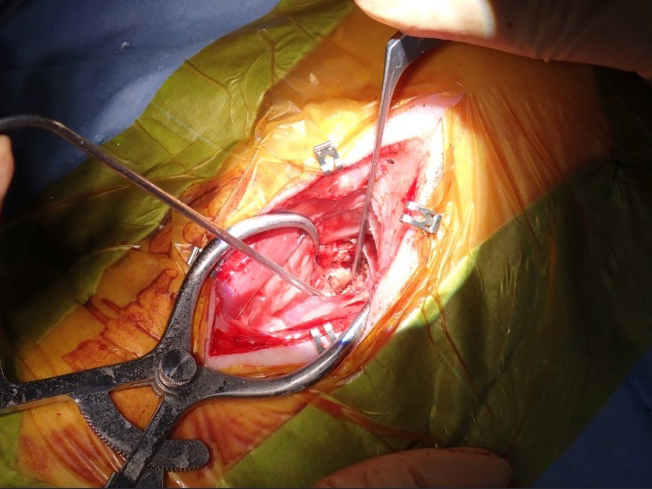

手術用顕微鏡下での視野。椎間にアプローチするためのスロットの作製

手術中の様子

術創